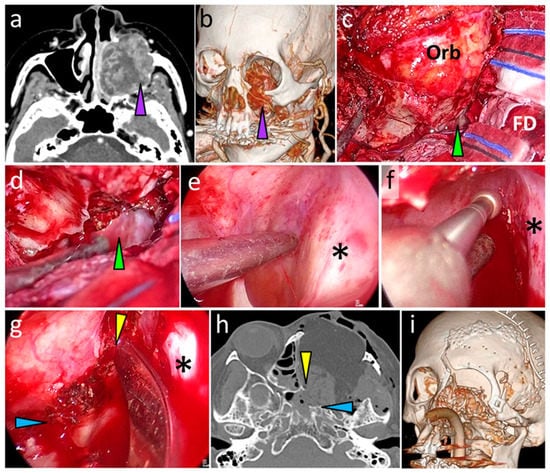

3.6.1. Case 1